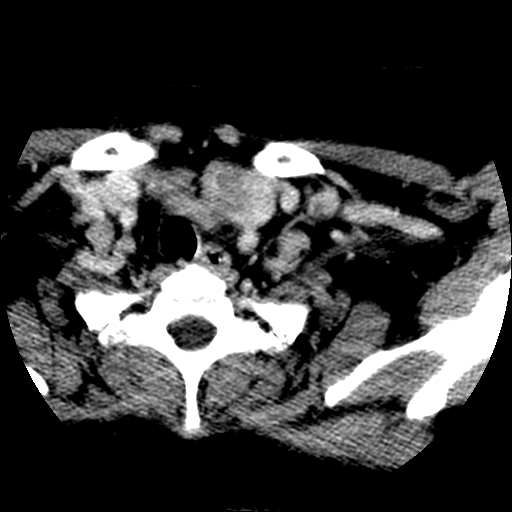

标题: CT25491:女,55岁,发现左侧甲状腺肿块一个月。 [打印本页]

标题: CT25491:女,55岁,发现左侧甲状腺肿块一个月。

女,55岁,发现左侧甲状腺肿块一个月,彩超示:甲状腺多发结节伴左叶结节液化。

边界清,无明显强化,考虑考虑甲状腺腺瘤

考虑左侧甲状腺腺瘤囊变。